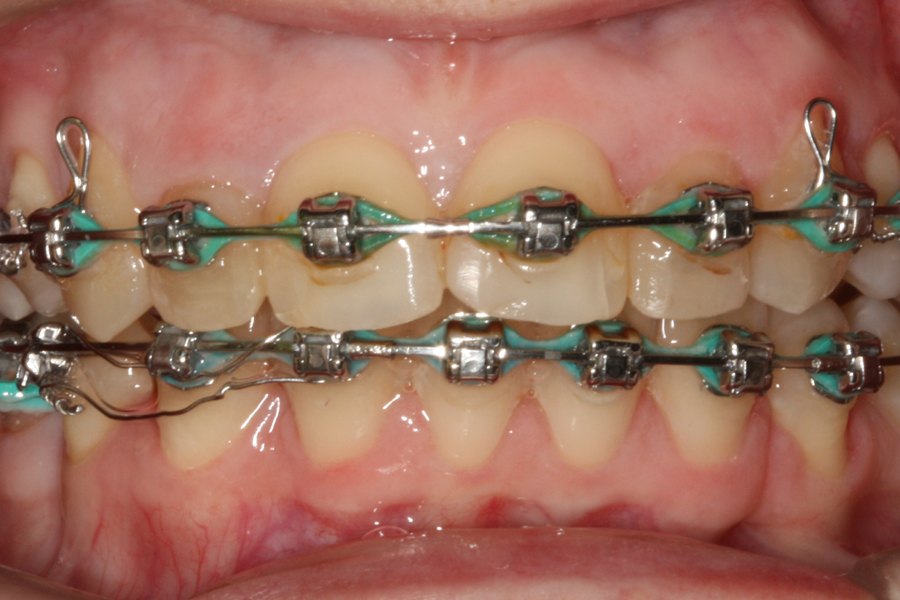

Kompleksowe leczenie zachowawczo-ortodontyczne

Młoda pacjentka zgłosiła się do naszego gabinetu celem wykonania kompleksowego leczenia zachowawczo-ortodontycznego. Oprócz problemów natury ortodontycznej stwierdzono złą higienę jamy ustnej oraz liczne potrzeby leczenia zachowawczo-endodontycznego. Po wnikliwej analizie telerentgenowskiej oraz analizie modeli zadecydowano o ekstrakcji 2 zębów w łuku dolnym (kła po stronie lewej oraz pierwszego przedtrzonowca po stronie prawej). Plan leczenia obejmował ponadto zamknięcie łuku po brakujących zębach w łuku górnym. Leczenie aktywne trwało 2 lata i 8 miesięcy. W czasie jego trwania pacjentka była regularnie poddawana zabiegom higieny profesjonalnej celem eliminacji zapaleń przyzębia brzeżnego. Po leczeniu aktywnym zastosowano leczenie retencyjne w postaci retainera stałego w żuchwie oraz szyny retencyjnej w łuku górnym.